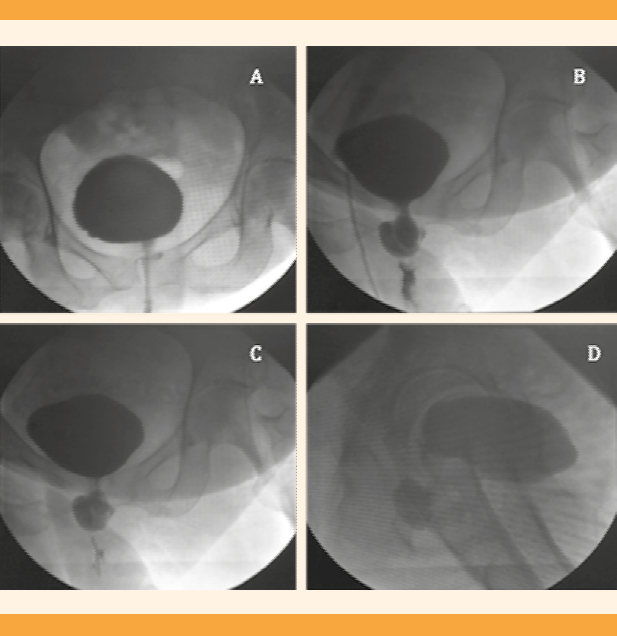

Al tacto vaginal se encontró una tumoración de 2 x 1 cm suburetral, dolorosa, 7/10 a la palpación. Se intentó realizar una cistoscopia de consultorio pero no fue posible debido al dolor. La cistouretrografía miccional seriada reportó un divertículo en el tercio medio de la uretra de 2.1 x 3.6 x 3.3 cm. (Figura 1) La resonancia magnética de pelvis en secuencia T2 evidenció saculación hipointensa en sentido anterior a la vagina con extensión alrededor de la uretra. Figura 2.

Figura 1 Cistouretrografía miccional seriada con medio de contraste hidrosoluble. A. Proyección anteroposterior con adecuado llenado vesical con paredes de bordes regulares. B. Dilatación del segmento medial de la uretra. C. Proyección oblicua-lateral derecha con dilatación del trayecto uretral. D. Proyección lateral con persistencia de la dilatación en relación con el divertículo uretral.